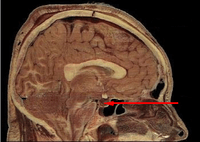

If secondary adrenal insufficiency is diagnosed, the insulin tolerance test (ITT) or the CRH (corticotropin-releasing hormone) stimulation test can be used to distinguish between a hypothalamic (tertiary) and pituitary (secondary) cause, but is rarely used in clinical practice.[16]

In some cases, actual cause of low ACTH is from low CRH in the hypothalamus. It is possible to have separate ACTH and CRH impairment such as can happen in a head injury.[17]